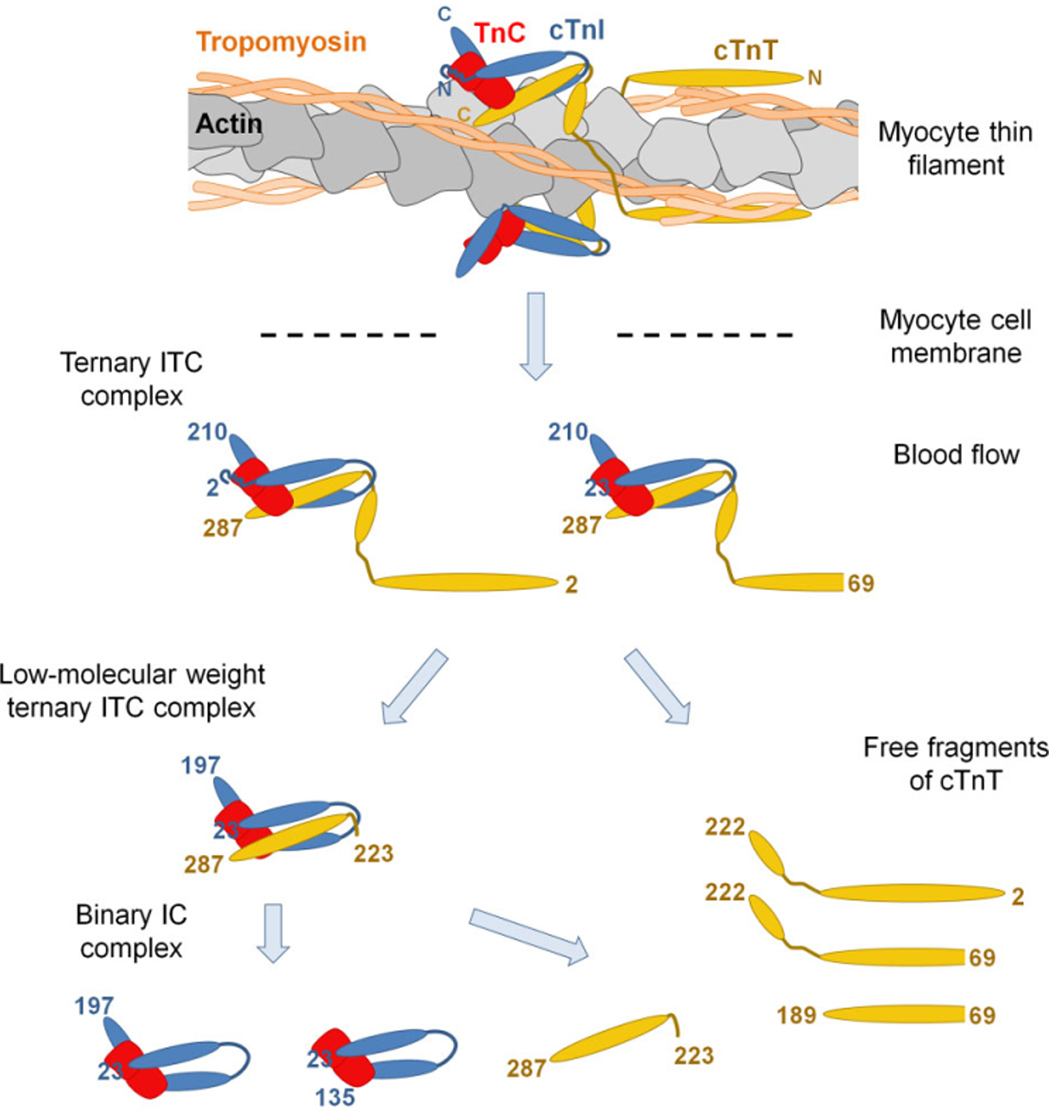

Scientists observed that after the onset of myocardial infarction, troponin is released from the heart into the peripheral circulation, and its complexes would appear in different forms over time. For over two decades, HyTest's moving increasingly close to the truth has pushed it into rethinking how to identify highly specific antibodies that can adapt to changes and deliver accurate test results.

Since troponin exists in a variety of forms, it is necessary to build a combat system to recognize complexes.

Based on the research on complexes, the scientists started to experiment on the recognition sites to identify the optimal capture/detection antibody pair. They intended to come up with a "proactive and adaptable" tactic to eliminate interferences and precisely capture targets in the molecular stabilization region.

Schematic illustration of cTnI testing system

1. Katrukha IA, Katrukha AG. Myocardial Injury and the Release of Troponins I and T in the Blood of Patients. Clin Chem. 2021 Jan 8;67(1):124-130.